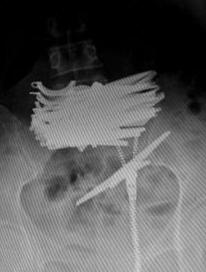

当天晚上,省直中医院急诊科对曲颖进行了抢救,随后送往普外科住院治疗,从X光片可见一捆剪刀横亘在其中下腹部,剪刀长近12厘米。医生诊断腹部肠管少量积气,未见明显液气平面和肠管扩张。

(X光图看到的女子体内剪刀)